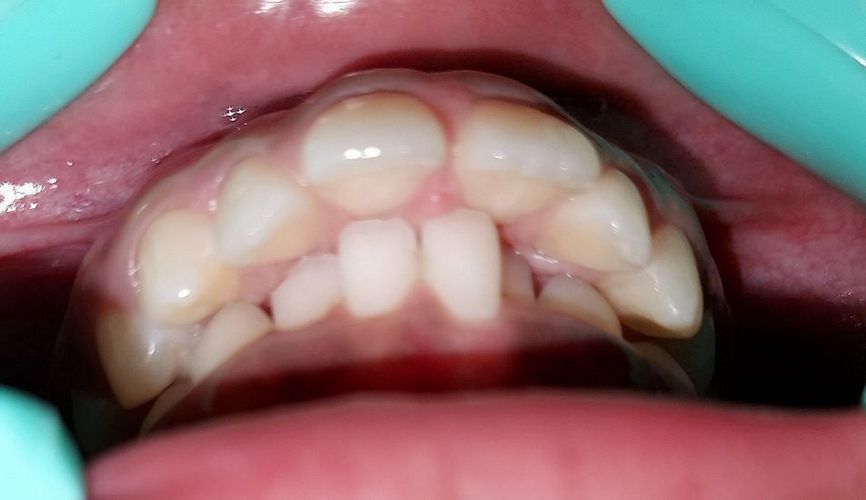

Case No: 12

Malocclusion Type: Crowding in Maxillary and Mandibular Anteriors

Mechanics: Anterior Crowding Relieved by Distalization of Mandibular Posteriors

Intra-oral : Pre-treatment : Frontal View

Intra-oral : Pre-treatment : Right Lateral View

Intra-oral : Pre-treatment : Left Lateral View